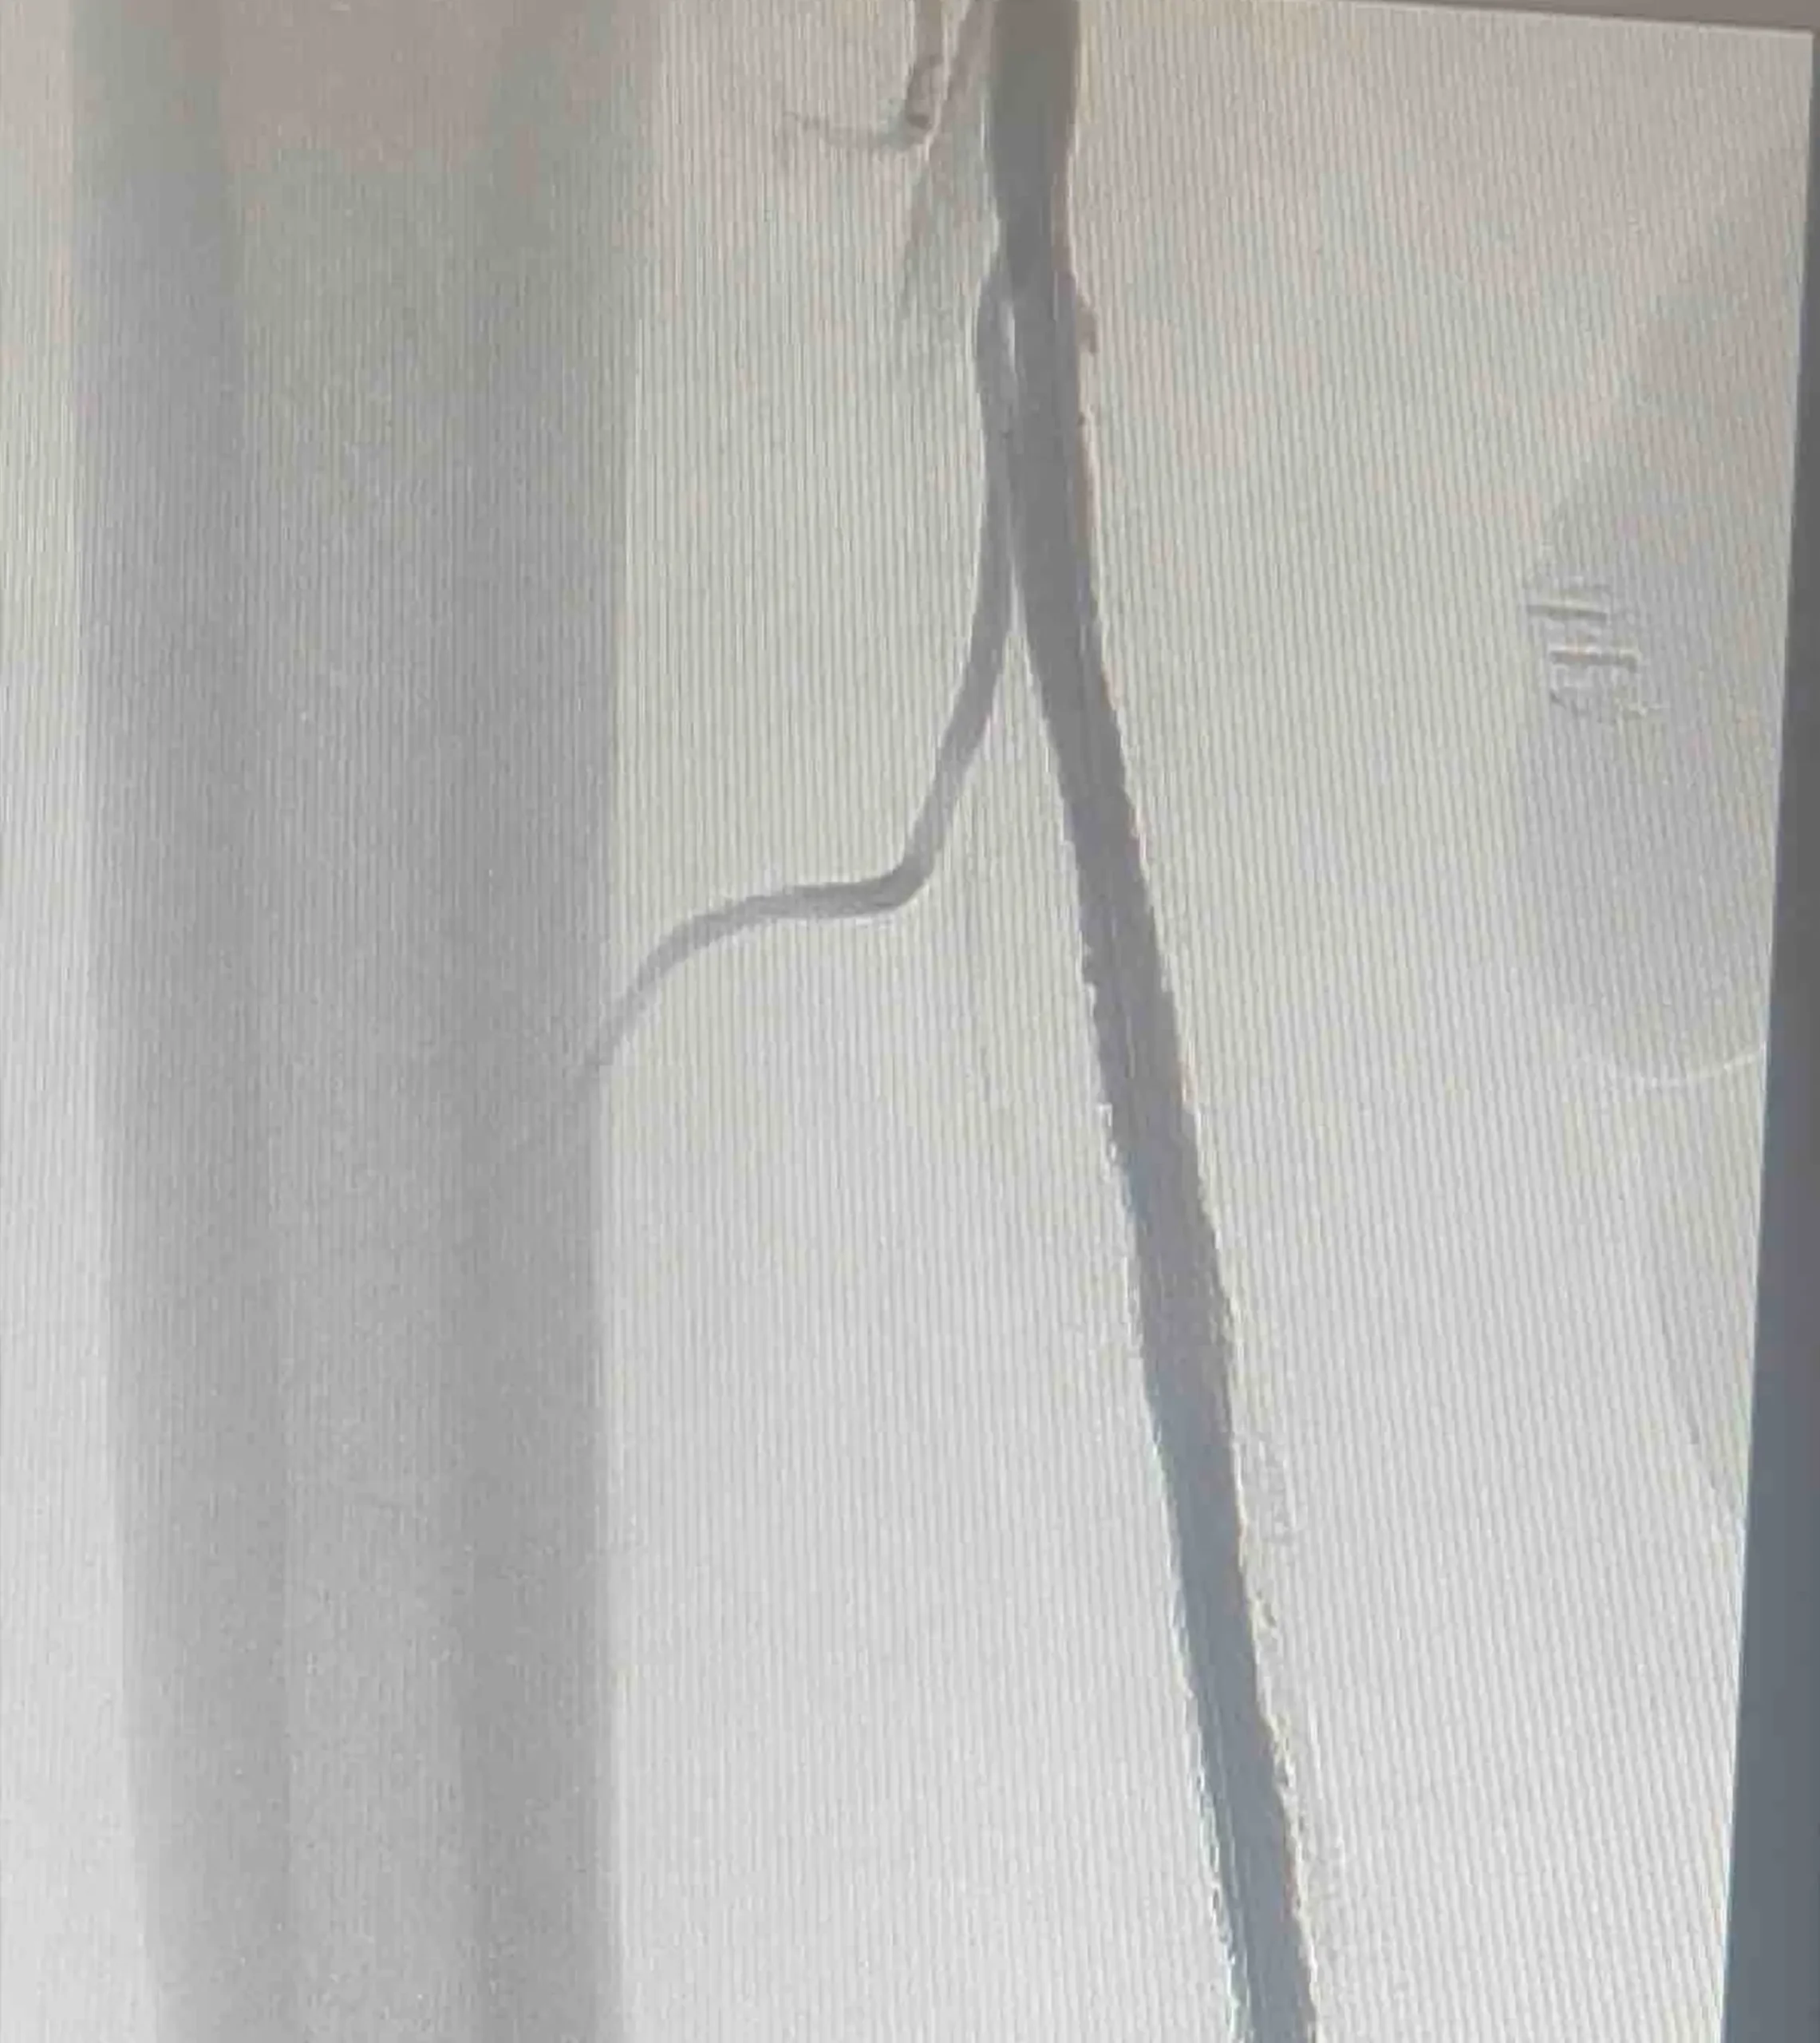

Dr. Akinrinlola is a highly skilled, board-certified vascular surgeon with extensive experience in both hospital-based and outpatient settings. Specializing in comprehensive vascular care, he has a particular focus on limb salvage, carotid interventions, peripheral interventions, dialysis access, and aneurysmal repair. His clinical expertise covers the full spectrum of vascular and endovascular procedures.